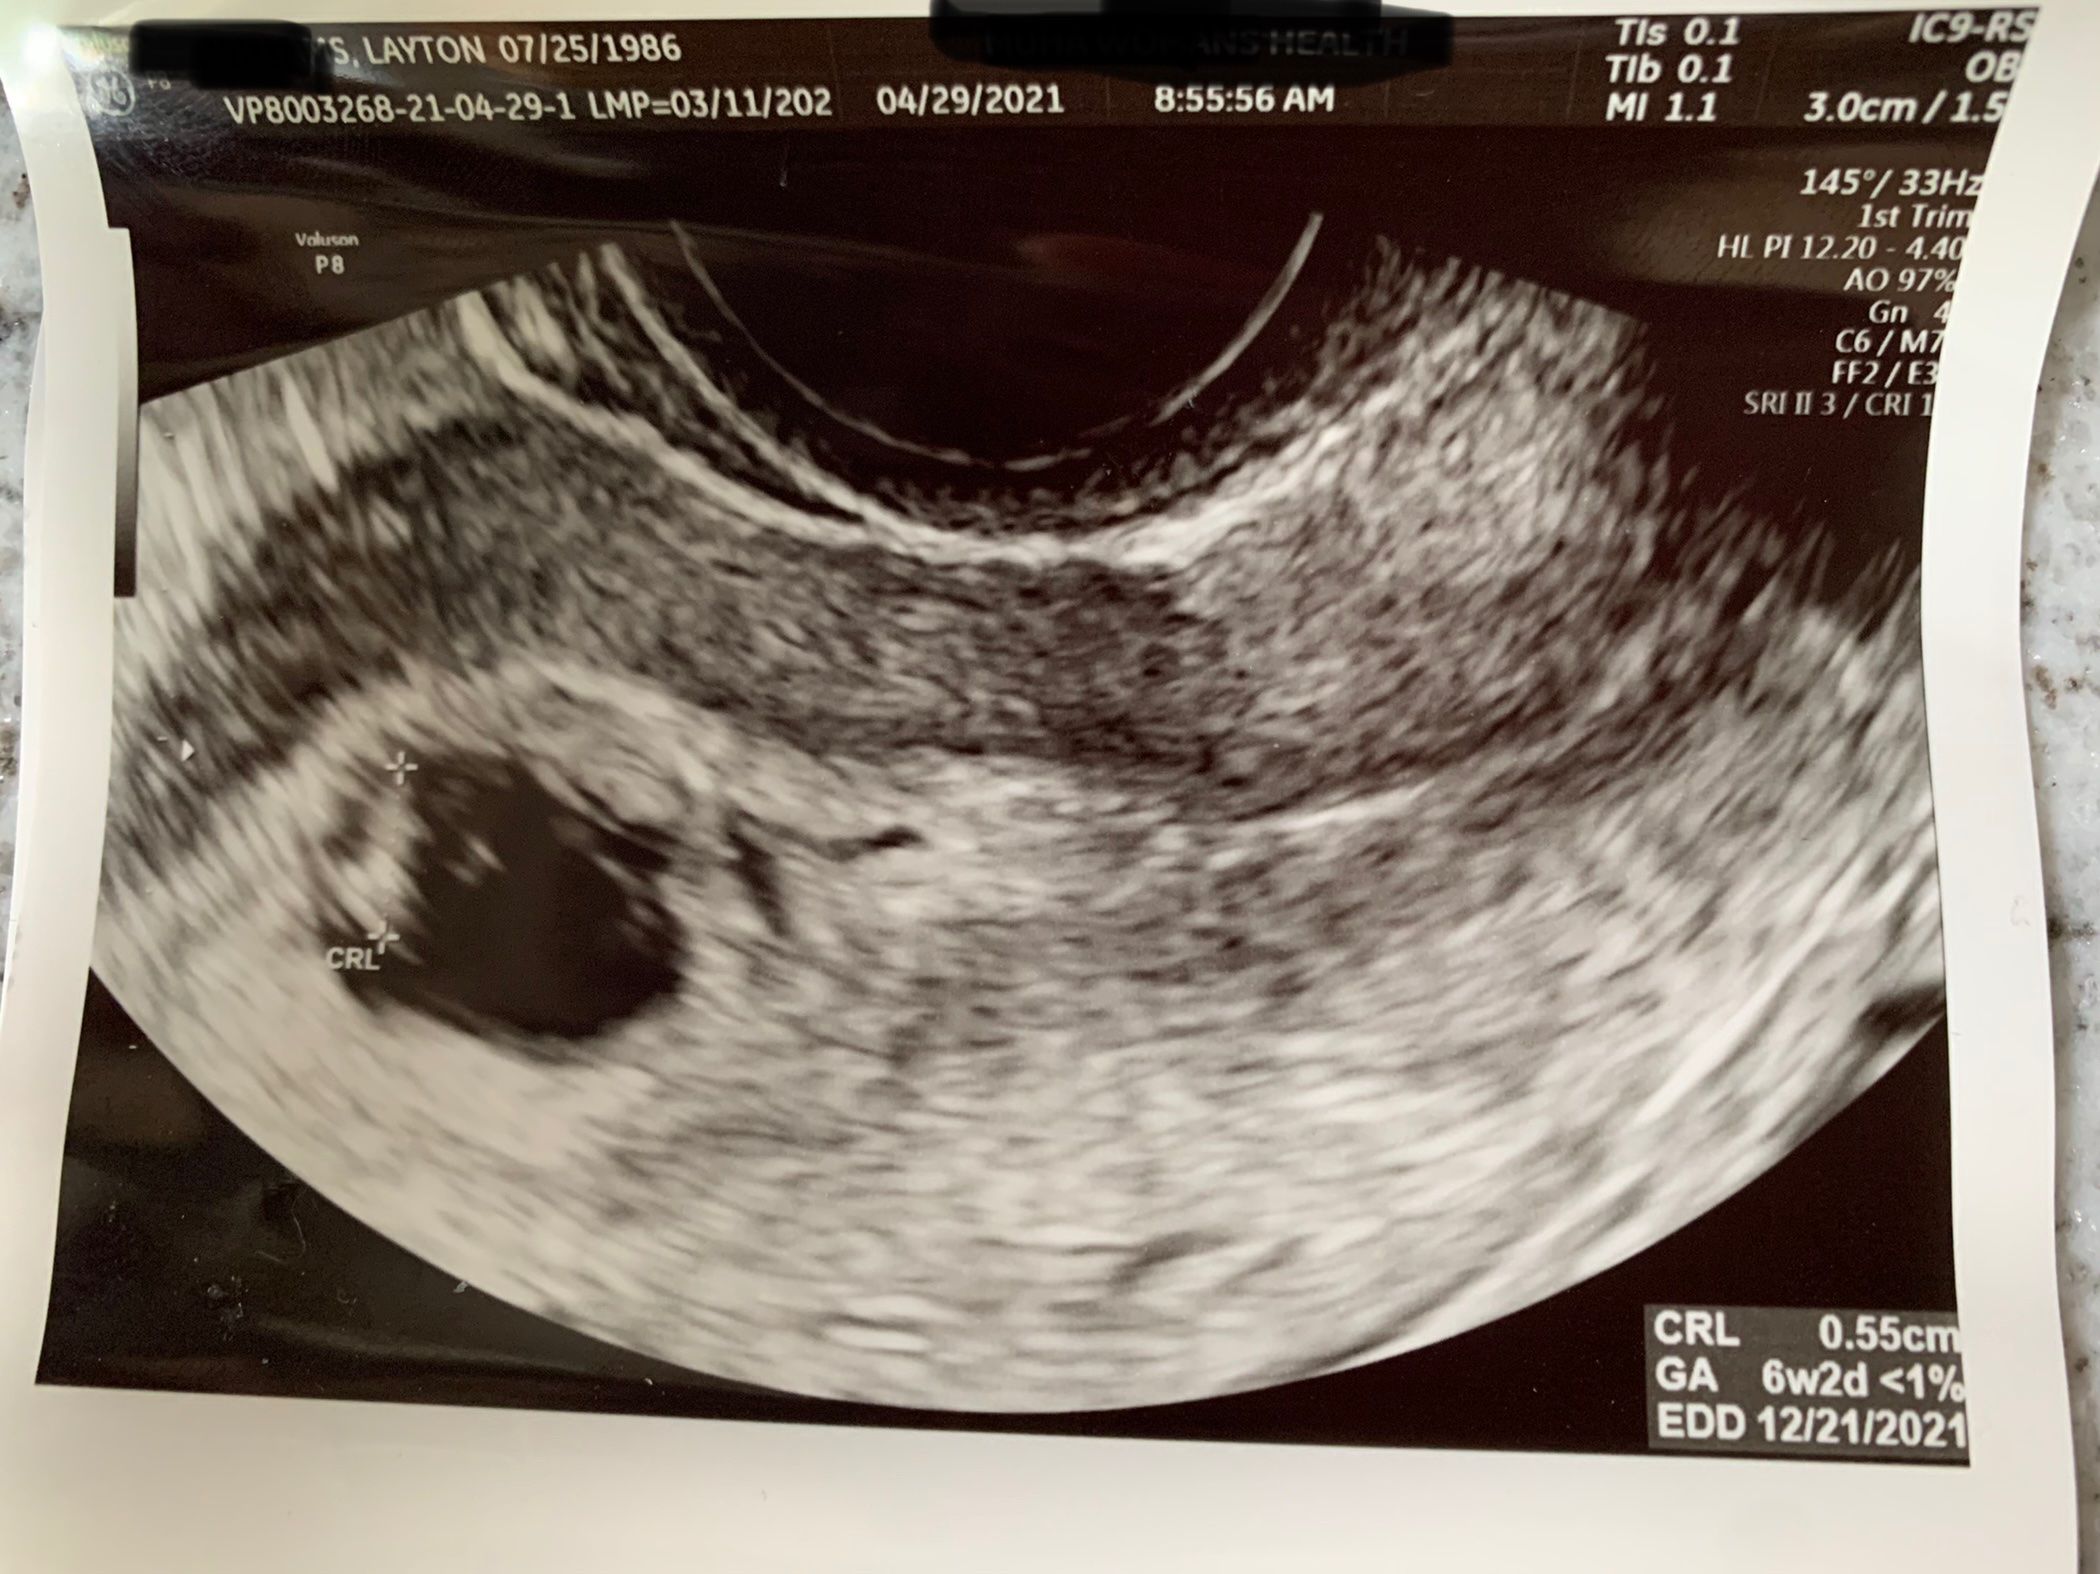

Hi there, I'm about 7 weeks along and I got a transvaginal ultrasound last week that I'm trying to find where the placenta is (or will be) to test out Ramzi theory for fun. I'm just having a hard time finding it. Anyone have some insight or a guess as to where it is in this image? Thanks!